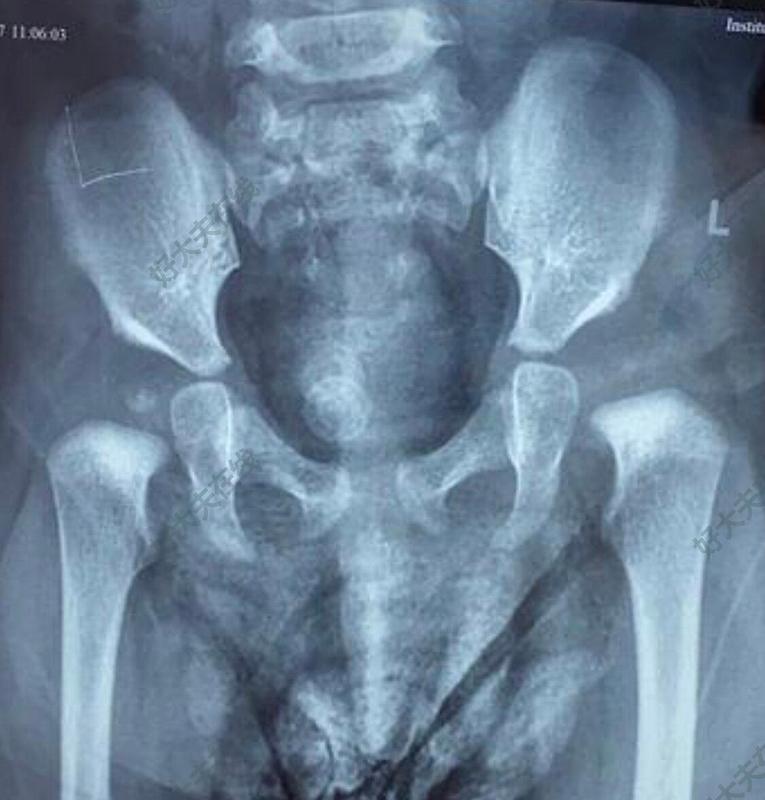

- 精選 發(fā)育性髖關(guān)節(jié)發(fā)育不良

治療前 雙側(cè)髖關(guān)節(jié)發(fā)育不良,左側(cè)嚴(yán)重,髖臼指數(shù)達(dá)到40度以上,做磁共振提示存在半脫位。 治療后 治療后7月 繼續(xù)固定1個(gè)月后不能耐受,自行去除支具,目前治療后7個(gè)月隨訪。髖臼指數(shù)恢復(fù)至28度。 治療后5月 2個(gè)月拆除,外展支具固定3個(gè)月復(fù)查 治療后即刻 人類位石膏固定